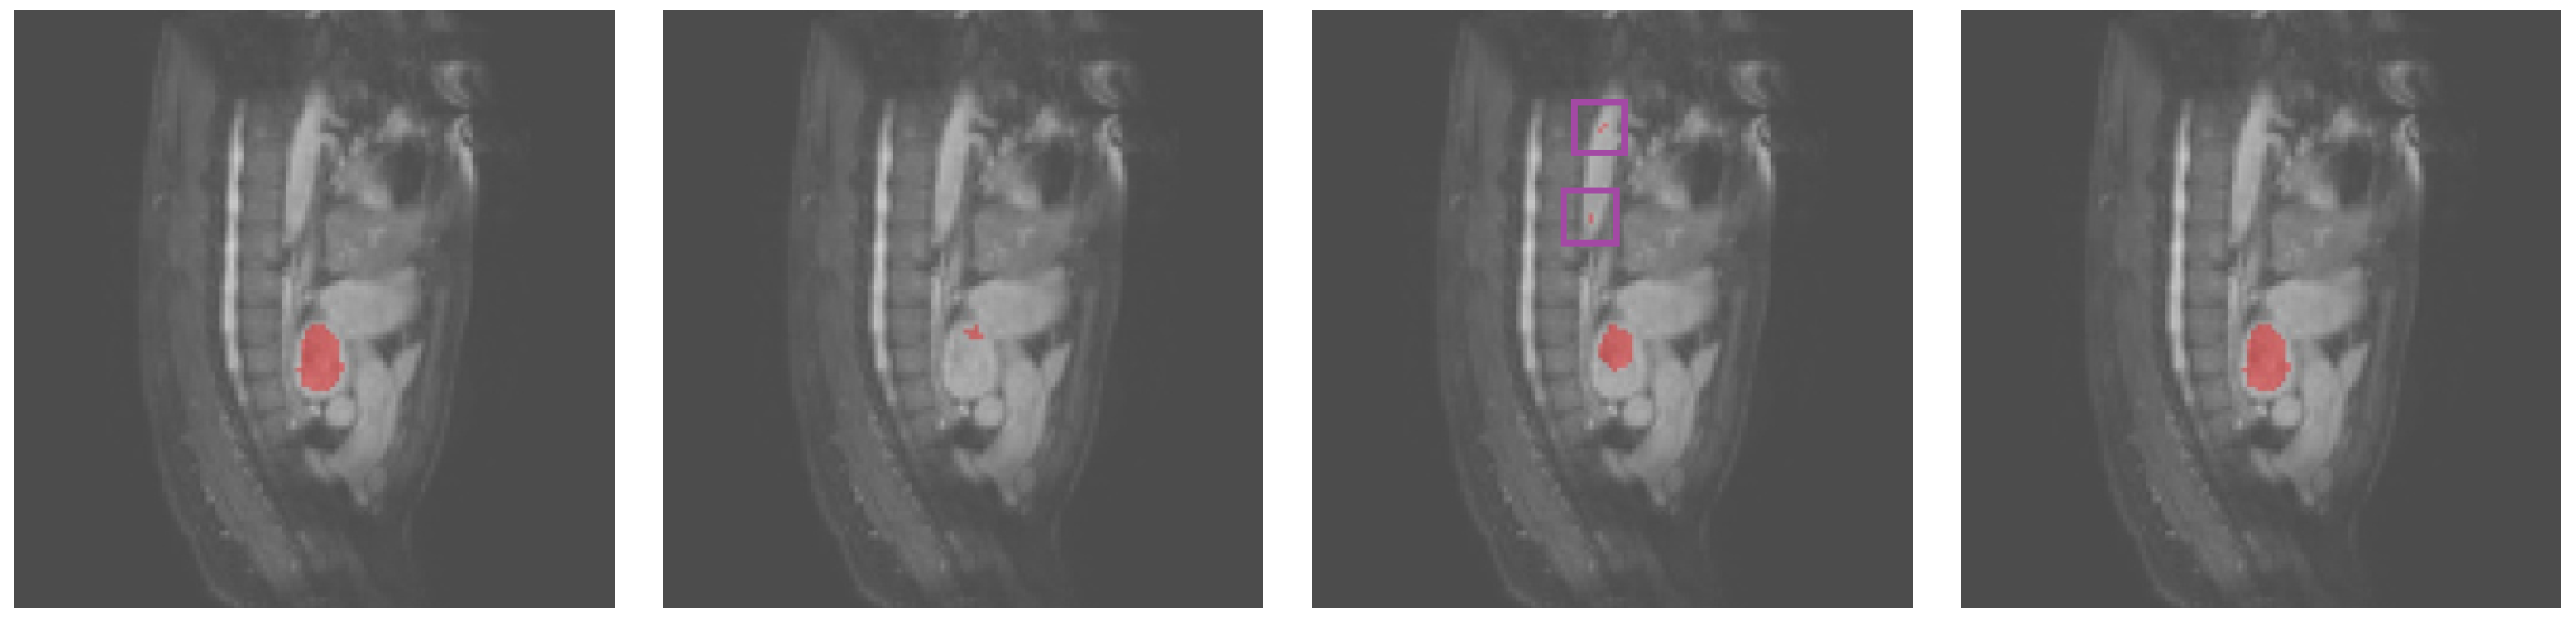

Table 4 demonstrates the successful application of SAB-Net to ventricular segmentation and the superior performance compared with that of existing approaches based on the validation results obtained on the Heart MRI dataset. SAB-Net’s average Dice value exceeded that of U-Net, the baseline, by 35.32%. We argue that the degradation problem caused U-Net to have very low Dice scores on the Heart MRI dataset. When increasing the network capacity with depth, the network performance became unsurprisingly saturated and was then quickly degraded [2]. This was also verified by our experiments, as shown in Table 4. Figure 3 illustrates an example of qualitative results obtained by U-Net, Att-UNet, and SAB-Net for the Heart MRI images.

Figure 3.

Qualitative results obtained for the heart MRI images. From left to right: ground truth, U-Net, Att-UNet, and SAB-Net.